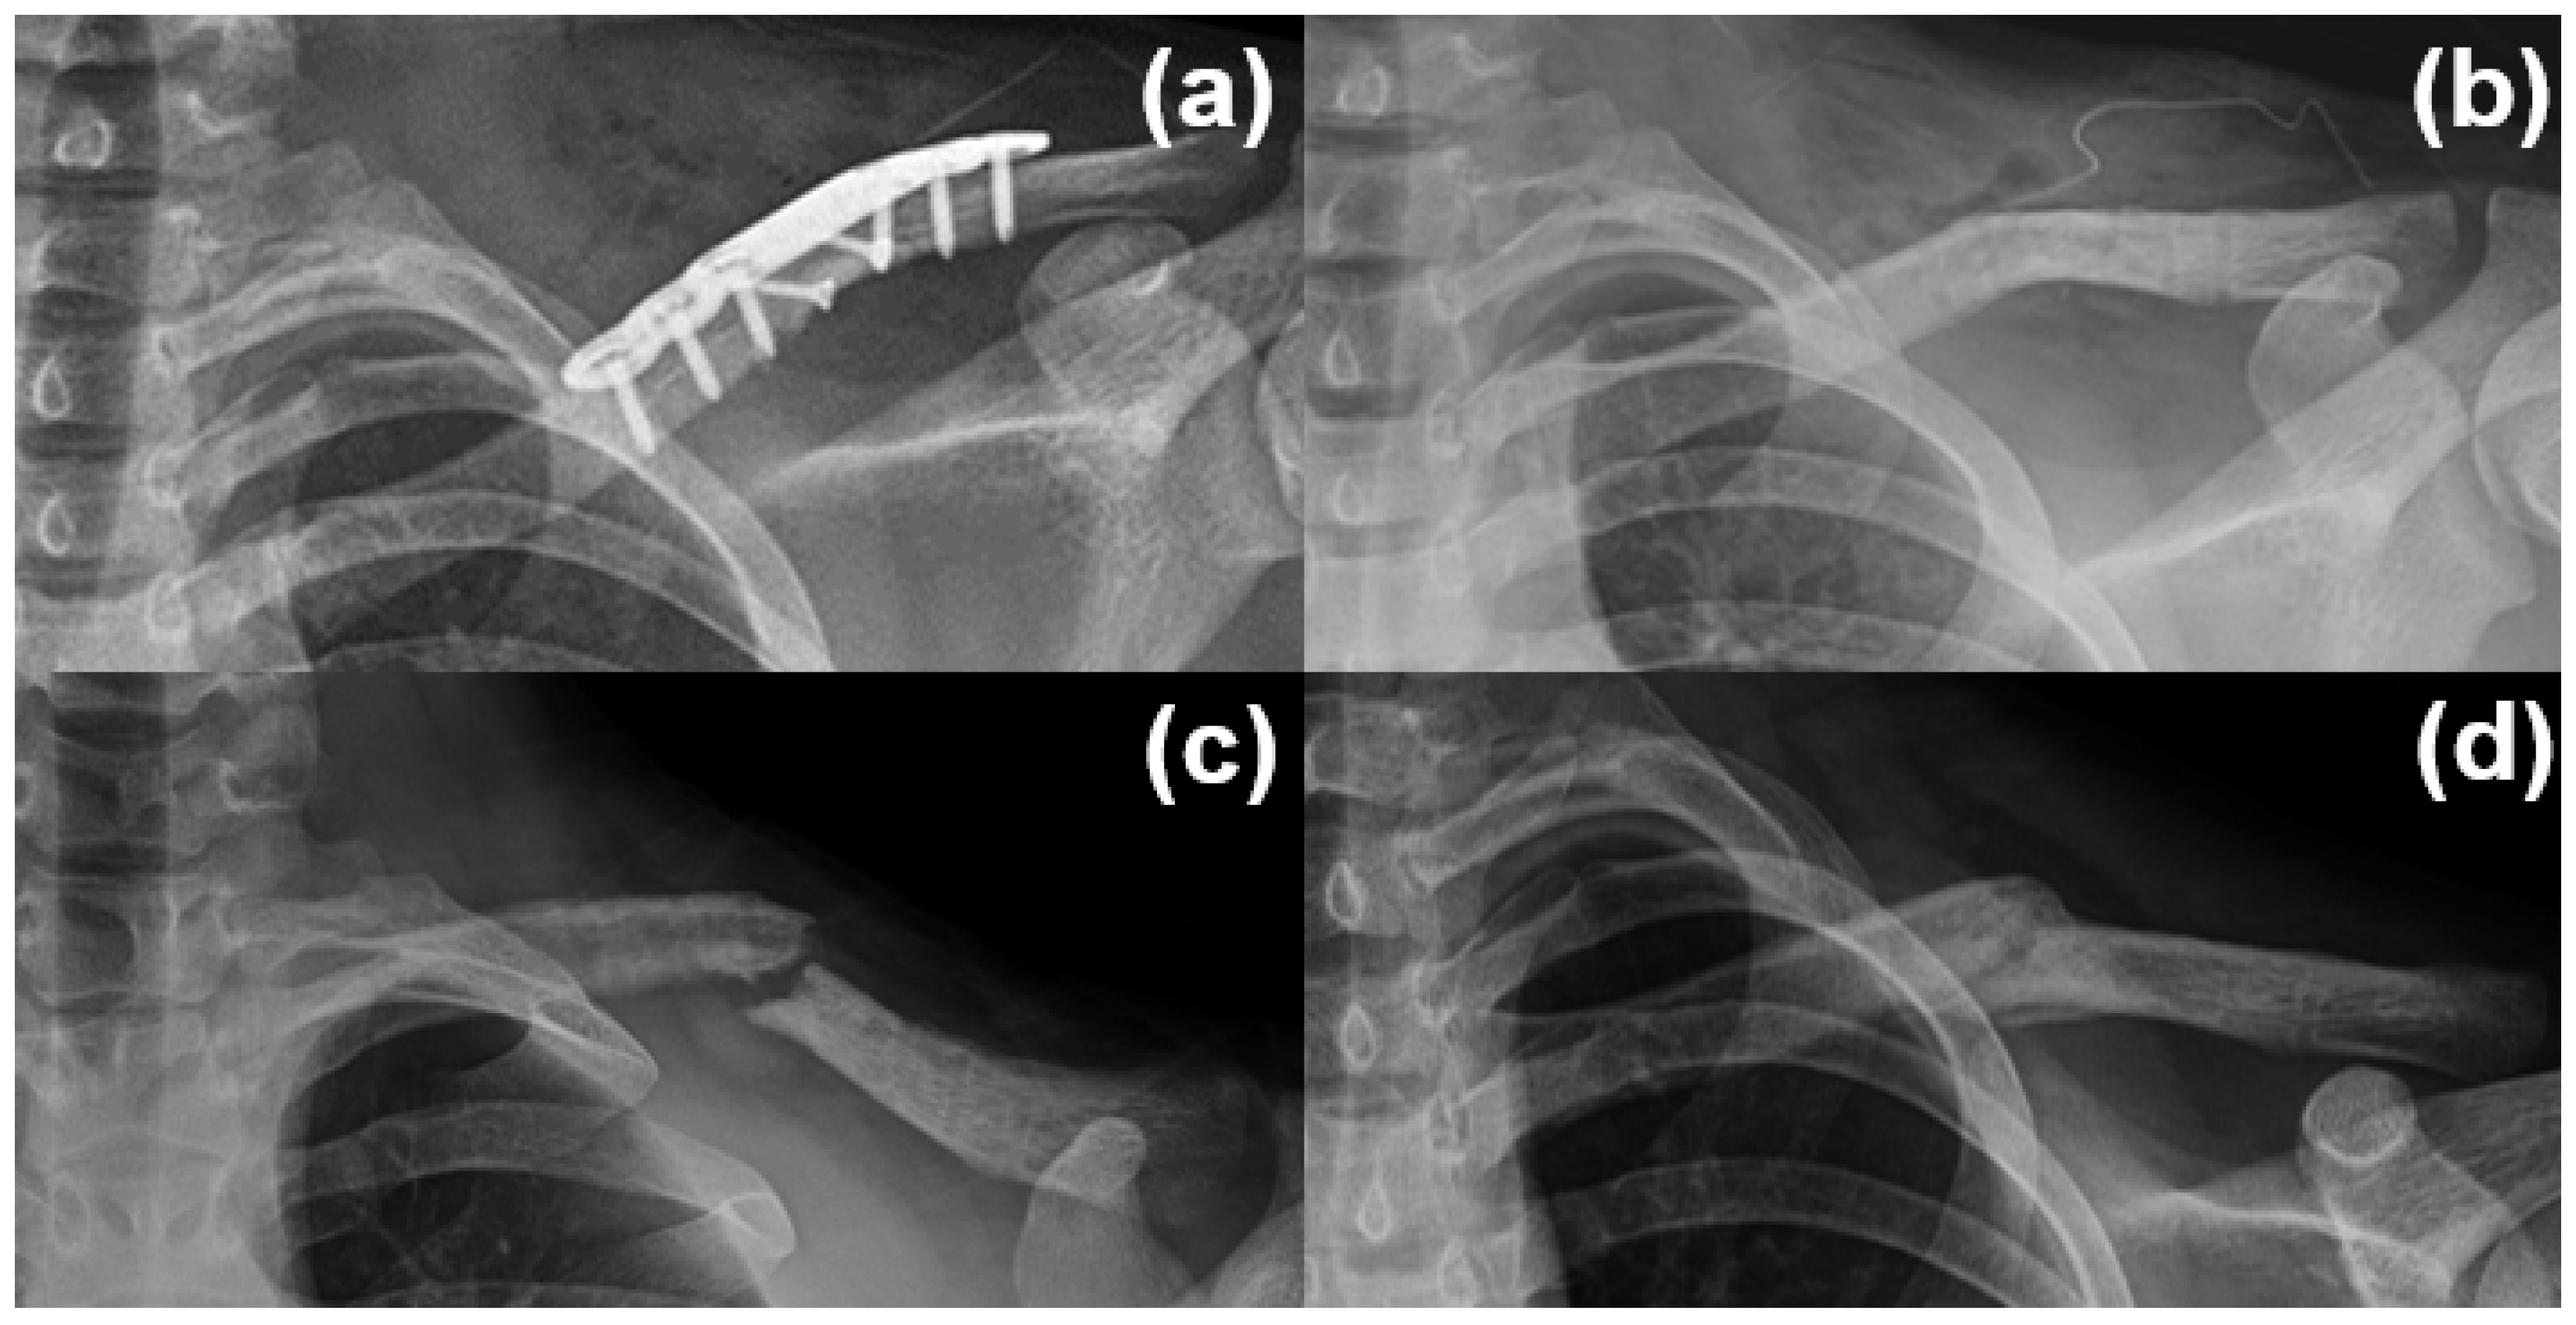

2.1. Operative Indications, Surgical Techniques, and Postoperative Management